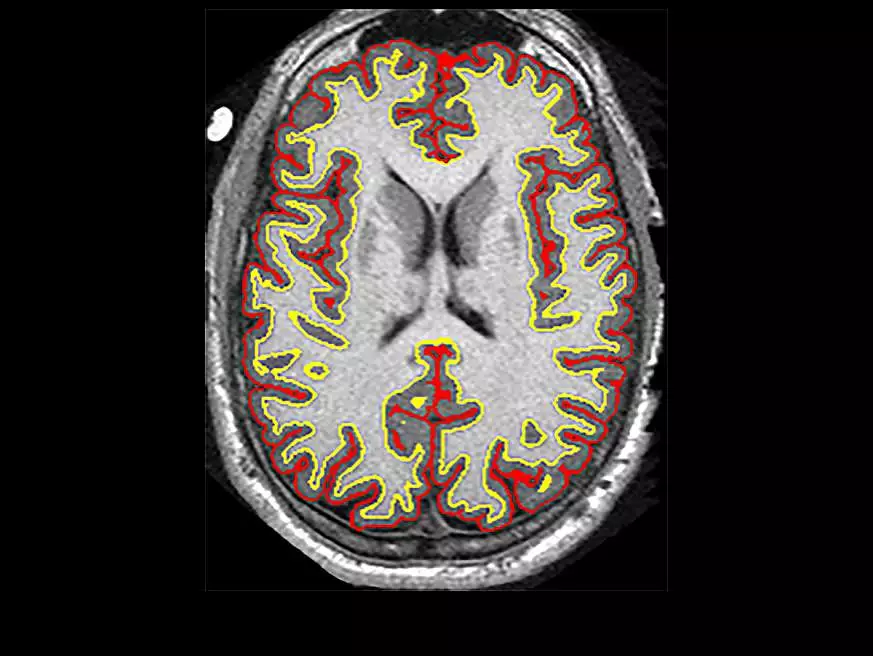

MS是一种中枢神经脱髓鞘疾病。髓鞘质(如上图)是一种缠绕在轴突周围的脂肪白色物质,是一种可以传递来自脑细胞信息的长链。当髓鞘质开始分解时,脑细胞之间的通讯减慢,导致肌肉无力以及运动、平衡、感觉和视力方面的问题。

在该研究中,255名患者被随机分配为两组,一组每天服用10粒异丁司特,另一组服用安慰剂,并持续96周。研究人员每6个月对参与者进行MRI脑部扫描。Fox博士的团队在MRI图像上应用了各种分析技术,以评估两组间大脑变化的差异。